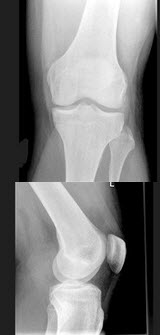

D.关节面破坏

男,根据其正常膝关节影像图像,判断其最可能的年龄()

A.61岁左右

B.51岁左右

C.11岁左右

D.21岁左右

E.31岁左右